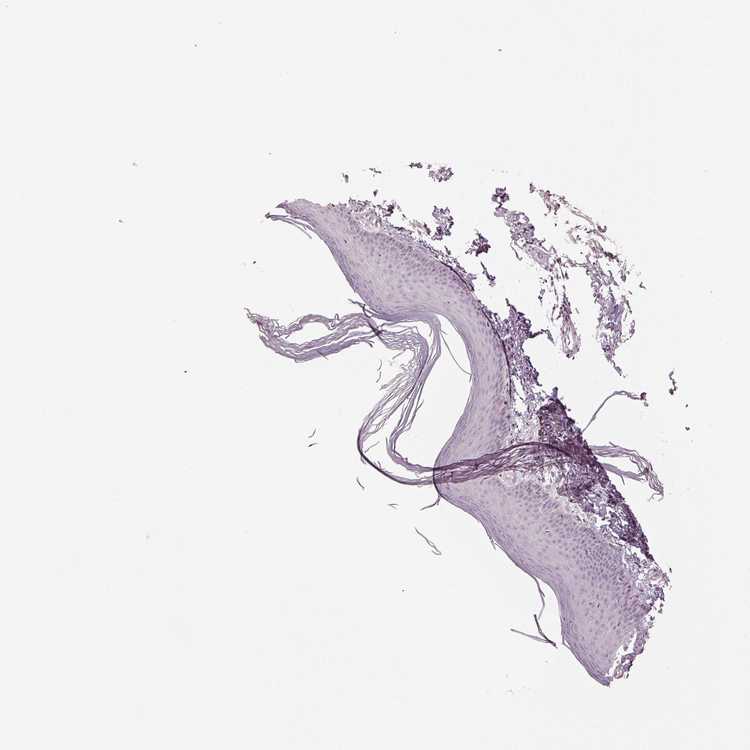

SKIN 1 - Antibody stainingi

Antibody staining in the annotated cell types in the current human tissue is reported as not detected, low, medium, or high, based on conventional immunohistochemistry profiling in selected tissues. This score is based on the combination of the staining intensity and fraction of stained cells.

Each image is clickable and will lead to virtual microscopy that enables deeper exploration of all samples and also displays staining intensity scores, fraction scores and subcellular localization as well as patient and tissue information for each sample.

Antibody HPA062655

Langerhans Not detected

Fibroblasts Not detected

Keratinocytes Not detected

Melanocytes Not detected